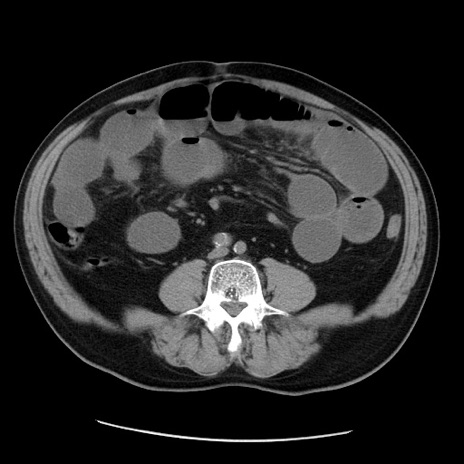

症例20(横断像)

【症例】 60歳代男性

【主訴】 腹部膨満、嘔吐

【現病歴】5日前頃より倦怠感を認め食事量減少し4日前の朝嘔吐、食事摂取困難となった。 3日前近医受診し点滴施行され整腸剤などを処方された。 当日他院を受診し、腹部膨満著明、炎症反応の上昇(CRP10.8、WBC11200)あり、紹介受診となる。

【身体所見】 意識JCS1 受け答えがはっきりしないBP 111/57mHg、 P 67bpm、、BT35.2°C、SpO2 97%(RA)、 腹部:膨隆、打診で鼓音あり、全体的に圧痛有り、腸蠕動音(-)、反跳痛ははっきりせず。

【データ】WBC 11400、CRP 14.20